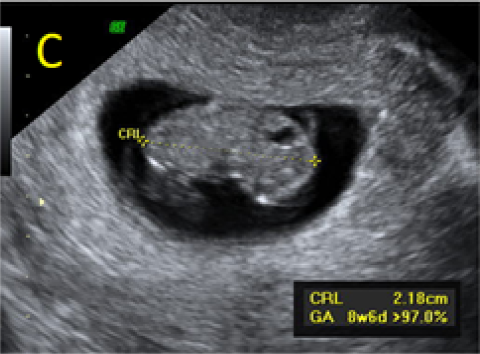

A 22-year-old secundigravida, presented to our Hospital with acute pelvic pain and vaginal bleeding. Her medical history included a 2-year prior caesarean delivery. The patient was in a stable condition and the clinical exam was unremarkable. As the urinary pregnancy test was positive, a transvaginal ultrasound scan was performed to evaluate the pregnancy location and viability. The exam revealed an empty uterine cavity but identified the gestational sac at the level of the caesarean scar with a live embryo (174 beats per minute), measuring 8 weeks and 5 days by crown-rump length. (Figures 1). Because the trophoblastic tissue was noted with an anteriorly location, urinary bladder invasion was suspected based on the ultrasonographic signs: poor identification of the bladder wall, the lack of the sonolucent space and increased vascularization with abnormal pattern (Figure 2). The patient blood tests results were normal, and beta-human chorionic gonadotropin (b-HCG) value was 145.000mUI/ml. After proper counselling and written informed consent the patient opted for a medical conservative treatment with desire to preserve her fertility.

Figure 1. A: the gestational sac is located at the level of the uterine isthmic scar, grey-scale and Power Doppler transvaginal evaluation. B: an embryo with a crown-rump length (CRL) that corresponds to 8 weeks and 1 day is found with normal fetal heart activity (C).